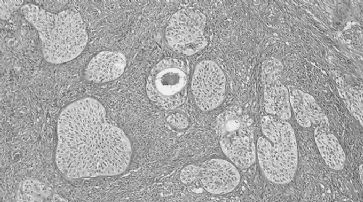

Eierstockkrebs: Neue Tests zur Früherkennung

Austin - Ein neues Verfahren zur Früherkennung von Eierstockkrebs haben Wissenschaftler der University of Texas entwickelt. Die ersten Forschungsergebnisse sind vielversprechend.

Tumore in den Eierstöcken sind im Frühstadium nur schwer zu erkennen. Daher kann es bei einer späteren Diagnose bereits zu spät für eine effektive Behandlung sein. An der Studie haben insgesamt 4051 Frauen teilgenommen. Laut dem Fachmagazin Cancer verfügt das Verfahren über das Potenzial, jene Frauen zu identifizieren, die eine Behandlung benötigen. Endgültige Ergebnisse über die Genauigkeit des neuen Tests werden 2015 erwartet. Protein CA125 richtig deuten

Die Überlebensrate bei Eierstockkrebs liegt bei bis zu 90 Prozent, wenn die Erkrankung frühzeitig erkannt wird. Bei einer späteren Diagnose liegt der Prozentsatz nur mehr bei weniger als 30 Prozent. Anders als bei anderen Krebsarten werden Symtome wie Schmerzen in Becken oder Bauch sowie langanhaltende Blähungen häufig als normale Beschwerden eingeschätzt und ein Tumor kann übersehen werden.

Bereits bekannt ist, dass die Werte des Proteins CA125 bei Eierstockkrebs häufig erhöht sind. Dieser Wert allein gilt jedoch als zu wenig aussagekräftig.

Manche Patientinnen werden dadurch nicht erfasst, bei anderen weisen diese Werte fälschlicherweise auf eine Krebserkrankung hin. Für die aktuelle Studie versuchten die Wissenschaftler basierend auf diesen Werten einen neuen Diagnoseansatz. Bei erhöhten Proteinwerten wurde nicht sofort zu einer Operation geraten. Bei geringem Risiko wurde der Test nach einem Jahr wiederholt, bei einem mittleren Risiko nach drei Monaten. Bei einem hohen Risiko wurde sofort eine Ultraschalluntersuchung durchgeführt.

Ultraschalluntersuchung wichtig

Die Teilnehmerinnen, die alle ihre Menopause bereits hinter sich hatten, wurden durchschnittlich elf Jahre lang von den Wissenschaftlern begleitet. Bei zehn Frauen wurde basierend auf den Ergebnissen der Ultraschalluntersuchung eine Operation durchgeführt. Bei allen wurde die Krebserkrankung frühzeitig diagnostiziert. Laut der leitenden Wissenschaftlerin Karen Lu ist es entscheidend, dass bei diesem Verfahren keine falsch positiven Testergebnisse festgestellt werden konnten.

Die britische Studie UKCTOCS mit 50'000 Teilnehmerinnen sollte jedoch endgültige Ergebnisse liefern. «Es gibt zwei grosse Fragen: Können wir die Krebserkrankung in einem früheren Stadium erkennen und können wir die Anzahl der Todesfälle durch Eierstockkrebs verringern?»